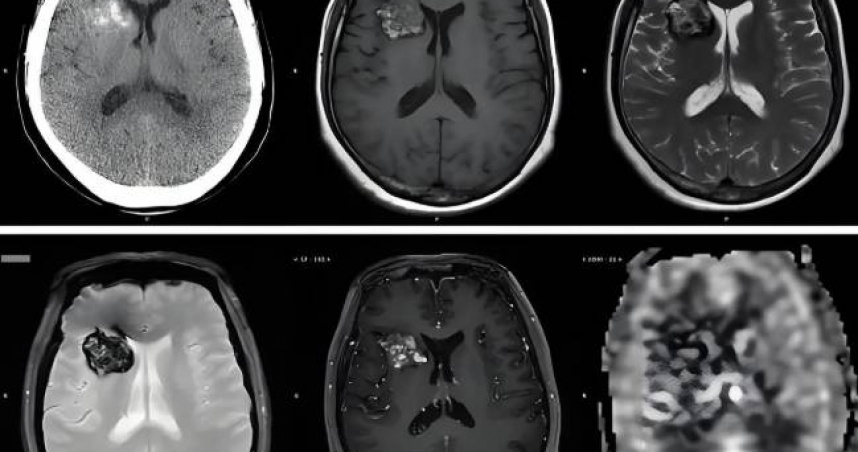

員工魏某經醫院診斷患有顱內血管瘤,醫囑明確要求避免熬夜。(圖/翻攝自MR亮哥說事)

案件顯示,魏某自2017年進入昆山某設備公司任職,2022年確診「顱內海綿狀血管瘤」與「腦血管畸形」,醫師明確建議避免熬夜。他隨即向主管報備,並提出不上夜班的需求,公司亦曾因此批准病假。但在明知魏某身體狀況的情況下,仍於2023年安排他從事夜班任務。魏某再次明確表達無法值夜班,理由合情合理,且並未影響公司正常運作。